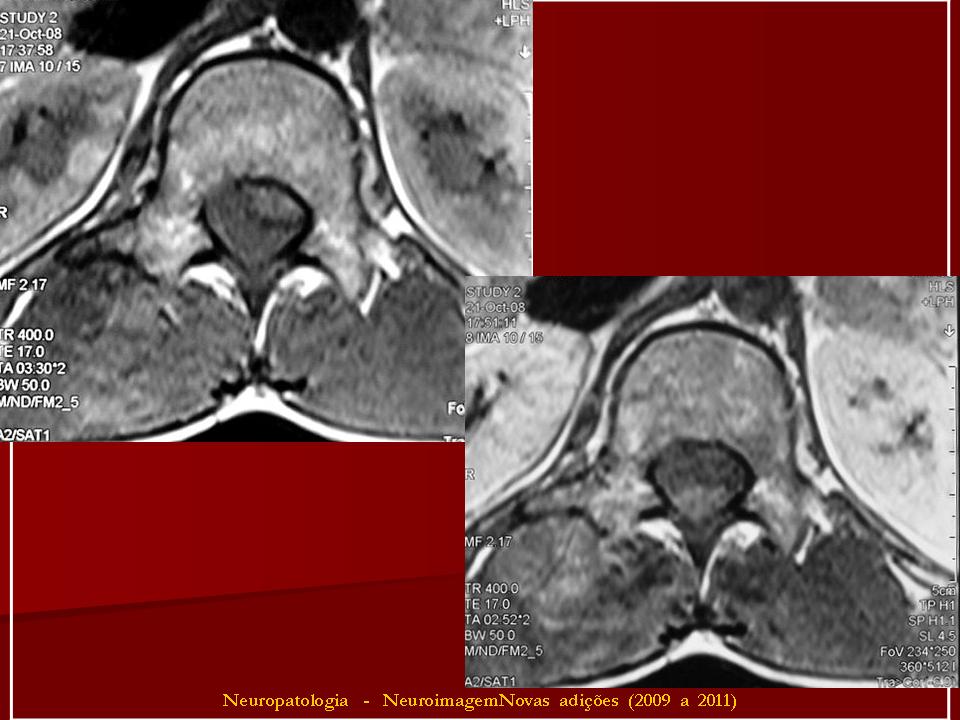

Примитивная нейроэктодермальная опухоль (pPNET)

Периферическая примитивная нейроэктодермальная опухоль (pPNET)